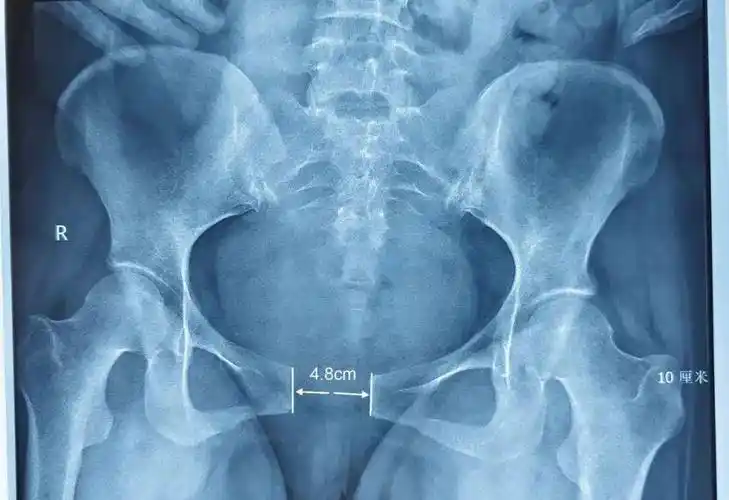

骨盆平片示:双侧耻骨结节局部骨质缺损,可见硬化边,耻骨联合变窄,边缘

48cm新晋宝妈直言自己痛到怀疑人生